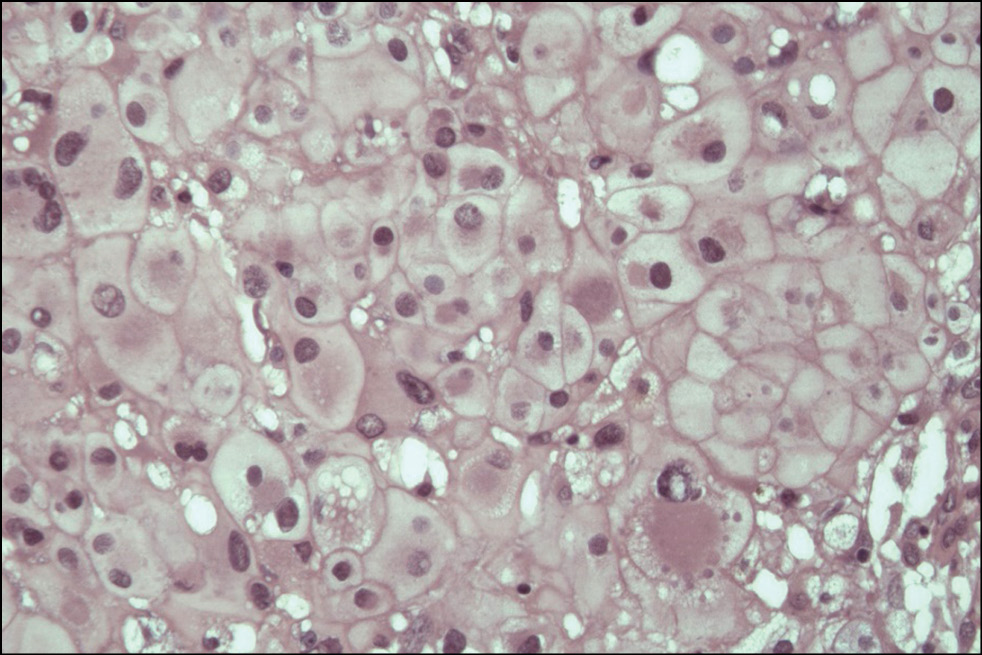

Histological examination of the surgical material revealed a solid neoplasm composed of strands or nests of epithelioid-type cells located in the mucoid intercellular matrix. The pathologic tissue was divided into lobules of different configurations and sizes by connective tissue layers. The tumor cells had large, rounded nuclei with moderate atypia and prominent nuclei. The cytoplasm was abundant and pale, with numerous cytoplasmic vacuoles, also known as physaliform cells (Fig. 10). In addition, epithelium-like cells with dense eosinophilic cytoplasm and weakly expressed vacuolization were found (Fig. 11). The cell population was predominantly mononuclear but also included binuclear and multinuclear cells, as well as cells with a ring-shaped vacuolized cytoplasm with the nucleus displaced to the cell membrane. Mitotic activity was low, and single atypical mitoses were detected. The tumor exhibited densely arranged syncytium-forming cells with a poorly expressed intercellular mucoid matrix in some areas, whereas other areas showed a predominance of the latter with only a few tumor cell islets. In addition, numerous necroses and hemorrhages were observed throughout the tumor.

Fig. 10. Micrograph. Conventional chordoma with characteristic physaliform cells with pronounced vacuolization of the light cytoplasm. Hematoxylin and eosin staining. ×400.

Thus, the histological picture is consistent with that of a conventional chordoma. The pathomorphologist reported that the resection margin was free of tumor (R0), confirming the surgery’s radicality.